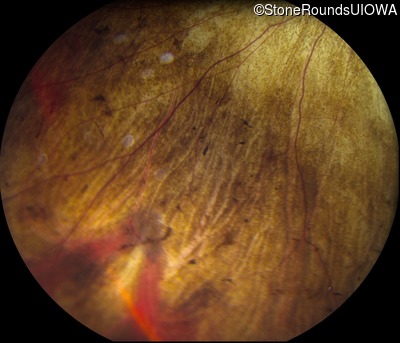

Fundus Photography - Right - 20/20 -2

Exemplar